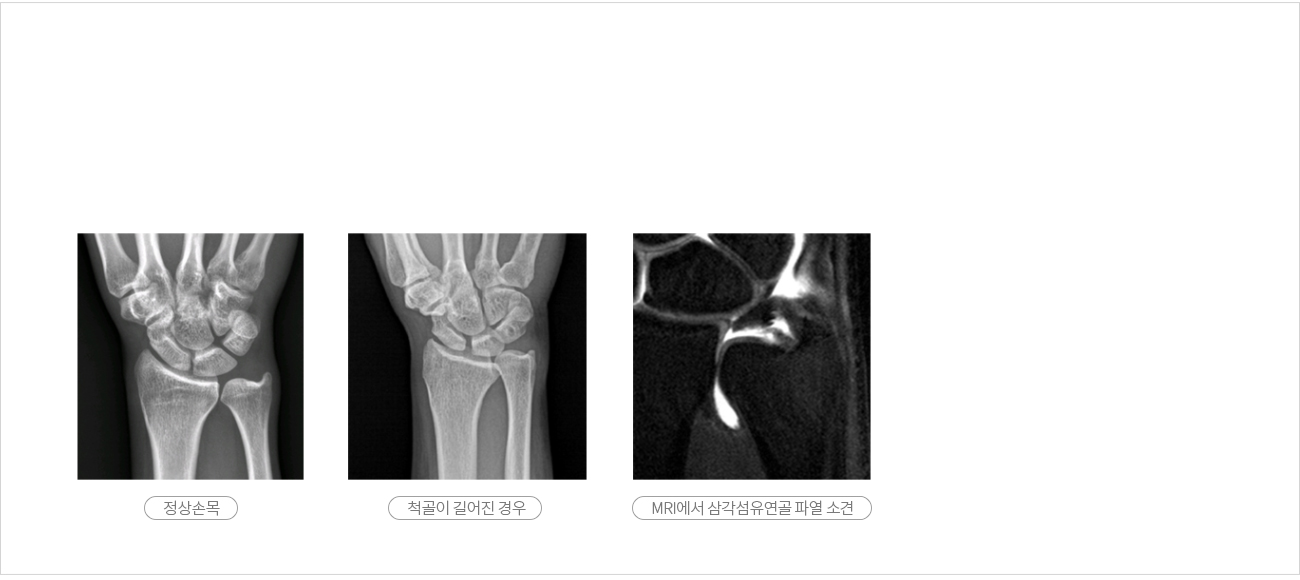

진단을 위해서는 의사의 검사 소견이 중요하며, 방사선 사진상에서 뼈의 길이변화를 관찰합니다.

MRI 상에서 인접 부위 손상 여부와 삼각섬유연골(TFCC)파열을 관찰할 수 있습니다.